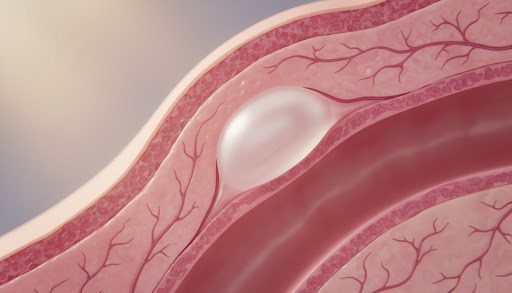

O cisto de retenção no colo uterino ocorre quando as glândulas produtoras de muco, localizadas na região do colo do útero, acabam sendo obstruídas. O colo uterino é revestido por diferentes tipos de células e possui glândulas que liberam o muco cervical, fundamental para a proteção do sistema reprodutor e para o processo de fertilidade. Quando o ducto de uma dessas glândulas é bloqueado, o líquido continua sendo produzido, mas não consegue ser expelido, formando uma pequena bolsa ou “bolinha”.

Essa obstrução glandular é um processo fisiológico comum, especialmente em mulheres que já tiveram filhos ou que passaram por processos de cicatrização na região cervical. É importante destacar que o cisto de retenção no colo uterino não é um tumor maligno nem possui relação direta com o desenvolvimento de câncer. Ele é apenas um acúmulo de secreção que ficou “preso” sob a superfície do tecido.

O diagnóstico do cisto de retenção no colo uterino é simples e visual. Durante o exame ginecológico com espéculo, o médico consegue visualizar pequenas protuberâncias esbranquiçadas ou amareladas na superfície do colo. A colposcopia, que utiliza um aparelho com lentes de aumento, permite observar essas lesões benignas com precisão, confirmando que se trata apenas de um acúmulo de muco cervical.